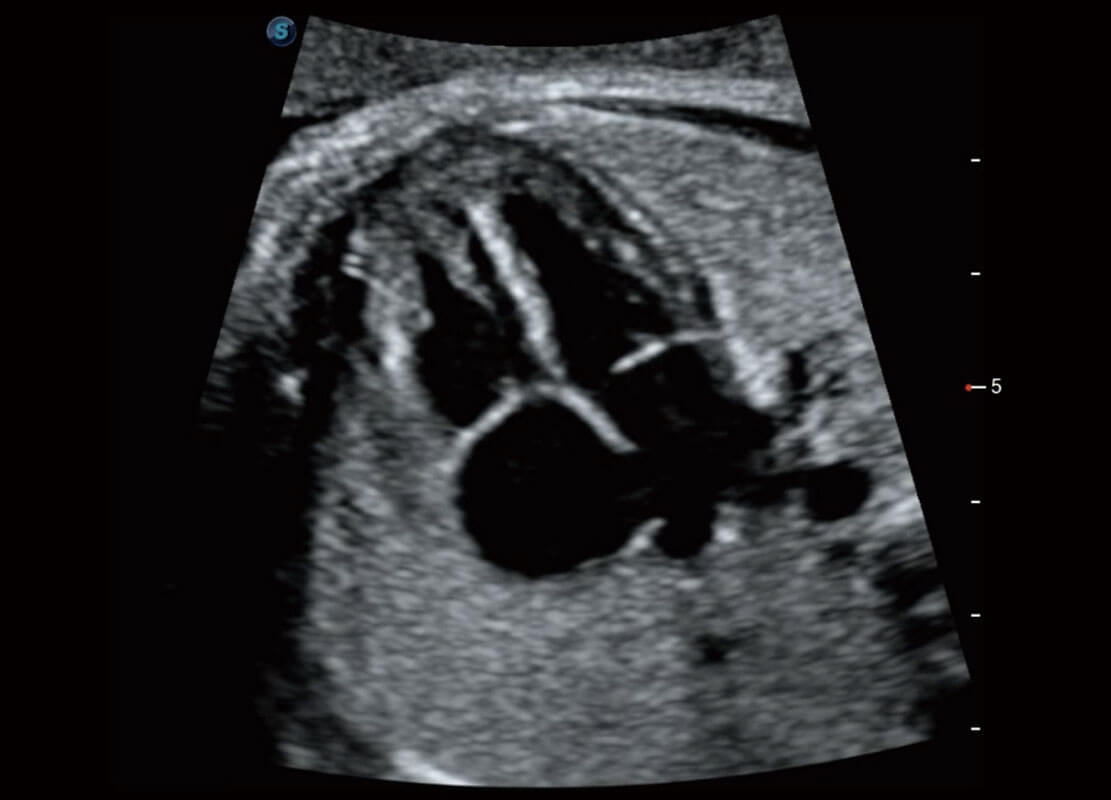

P60搭载一系列胎儿心脏成像技术,实现精细的胎儿心脏评估。

四腔切面

四腔心血流